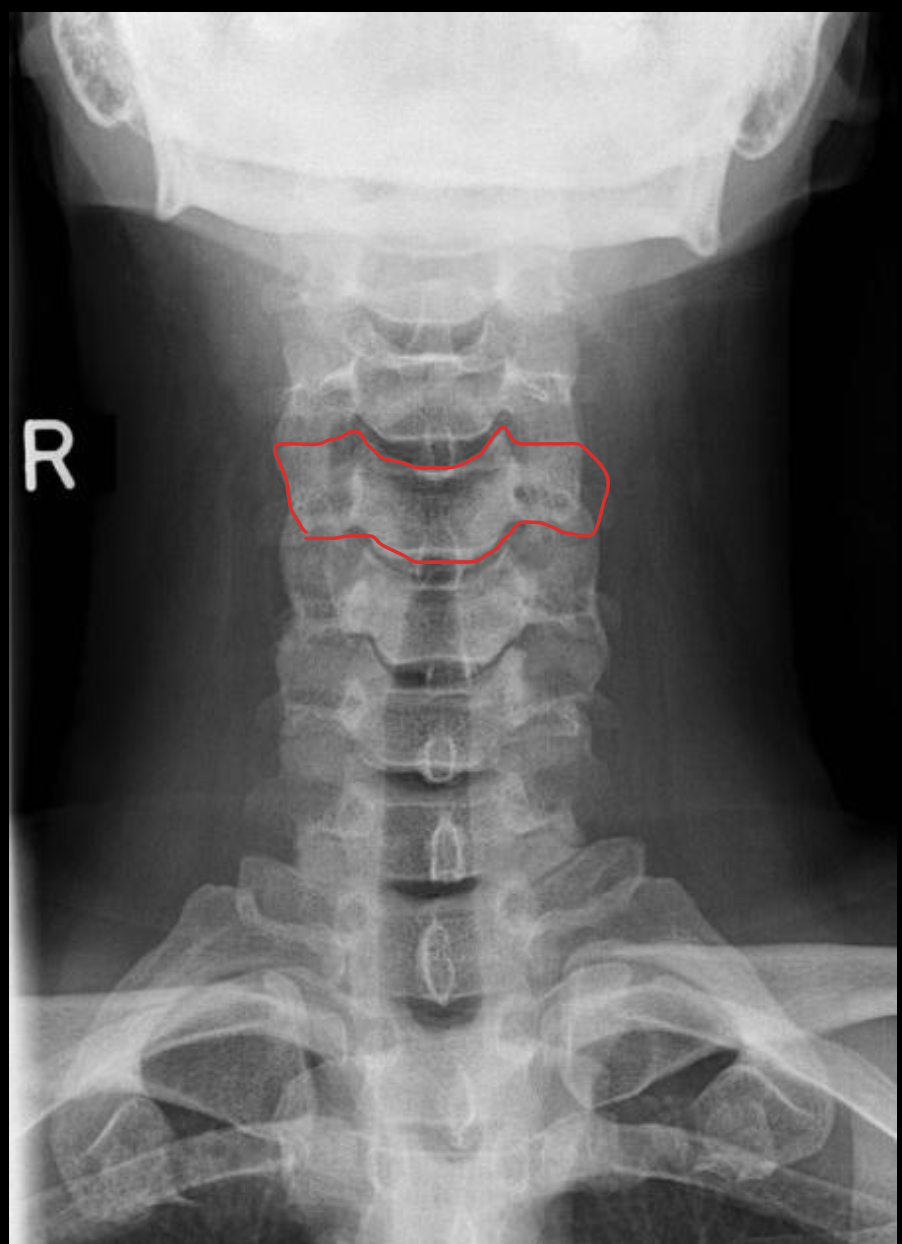

C2

C3

C4

c5

c6

c7

T1

1ST Rib

钩突

Uncinate process

关节柱 / 侧块

Articular pillars

棘突

Spinous process